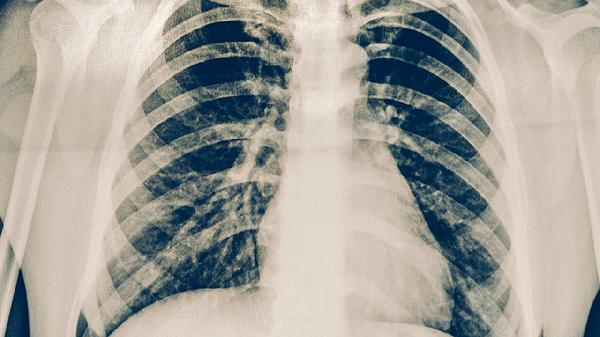

肺炎可能会引起胸痛,通常与炎症累及胸膜或肺部组织损伤有关。肺炎引起的胸痛多为呼吸时加重的钝痛或刺痛,可能伴随咳嗽、发热等症状。

细菌性肺炎或病毒性肺炎累及胸膜时,胸痛较为常见。炎症刺激胸膜神经末梢可导致单侧局限性疼痛,咳嗽或深呼吸时疼痛加剧。部分患者可能出现胸骨后闷痛,与炎症波及支气管或纵隔有关。此类胸痛多随抗感染治疗缓解,常用药物包括阿莫西林克拉维酸钾片、盐酸莫西沙星片、头孢呋辛酯片等。

重症肺炎合并胸腔积液或肺栓塞时可能出现持续性剧烈胸痛。大量胸腔积液压迫肺组织可导致呼吸困难伴胸部压迫感,肺栓塞则表现为突发尖锐胸痛伴咯血。这类情况需紧急医疗干预,可能需进行胸腔穿刺引流或抗凝治疗。